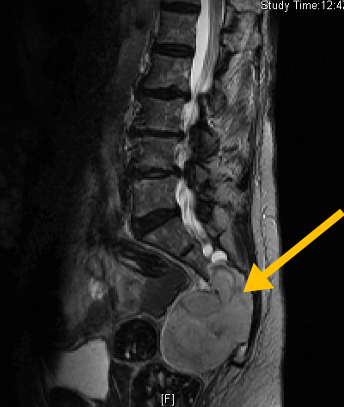

Chordoma is a slow growing (low-grade), cancerous (malignant) bone tumor. These tumors most commonly affect the sacrum, spine, or base of the skull.

It is a particularly rare and deadly type of chondrosarcoma. Approximately ⅔ of cases occur in the bone. and ⅓ in the soft tissues. Can metastasize to lungs, liver, lymph nodes and other bones.